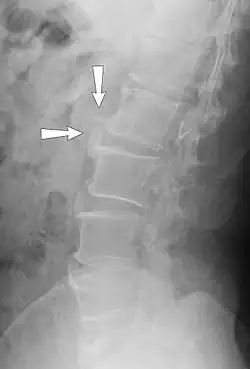

| Small marginal osteophytes (arrows) of the processus anconeus of the ulna can be seen in this gross pathological specimen of a sow. | |